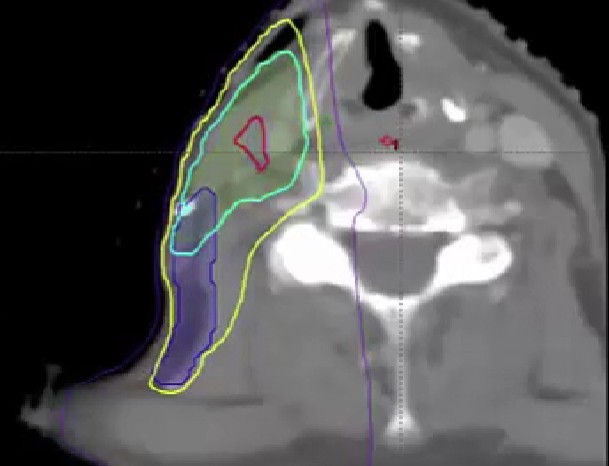

advanced skin cancer, paranasal sinus cancer, infratemporal fossa